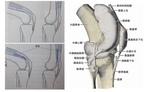

膝関節の問題

若い年代での膝の問題は、将来的にみれば変形性膝関節症に移行する可能性はおおくあります。

なぜなら、半月板や関節などの組織は1回壊すと元に戻る事はないからです。